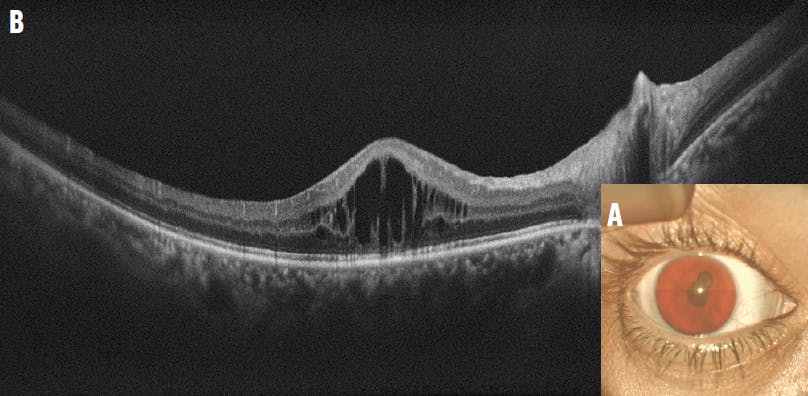

A 37-year-old woman presented with decreased vision in her right eye for 3 years and a VA of 6/60. The anterior segment examination showed posterior synechiae with a festooned pupil and complicated cataract (Figure 6A). The patient noted a history of recurrent attacks and had recently completed a course of oral steroids with immunosuppressants. On OCT, the foveal contour was altered with multiple cystoid spaces in the right eye (Figure 6B). The patient received a dexamethasone intravitreal implant (Ozurdex, Allergan/AbbVie) followed by cataract surgery with synechiolysis.

<p>Figure 6. The anterior segment examination showed posterior synechiae with a festooned pupil and complicated cataract (A). OCT showed an altered foveal contour with cystoid spaces (B).</p>

Figure 6. The anterior segment examination showed posterior synechiae with a festooned pupil and complicated cataract (A). OCT showed an altered foveal contour with cystoid spaces (B).